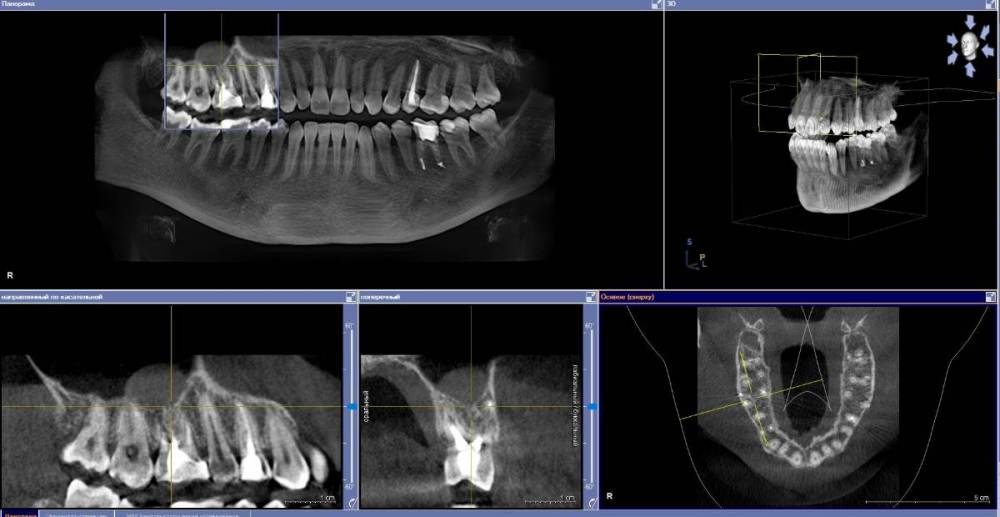

anishuma Опубликовано 1 сентября, 2021 Поделиться Опубликовано 1 сентября, 2021 (изменено) Здравствуйте, прошу помочь разобраться с моими КТ и направить для дальнейших действий. История такая: в 2018 году шестой зуб сверху справа был депульпирован. Долго сохранялись боли при нажатии, при жевании, зуб реагировал на холодной и горячее. Врач, который лечил, заверила что это постпломбировочные боли и скоро пройдет. Коронку побоялась ставить из-за этих болей. Затем примерно через год отлетел кусочек пломбы. Зуб восстановили для дальнейшей установки коронки. На данный момент есть ощутимая реакция на давление, при жевании, при чистки зубной щеткой. Зуб реагирует на холодное-горячее. Один врач сказал, что не видит показаний для перелечивания каналов. Другой врач настаивает на удалении зуба. Подскажите, пожалуйста, где истина, и возможно ли сохранить зуб. Изменено 1 сентября, 2021 пользователем anishuma Ссылка на комментарий

Bier Опубликовано 2 сентября, 2021 Поделиться Опубликовано 2 сентября, 2021 похоже что есть гранулема на корне 2 Ссылка на комментарий

St. Опубликовано 3 сентября, 2021 Поделиться Опубликовано 3 сентября, 2021 +1 к гранулеме. Я бы перелечивала каналы. Но нужно в процессе будет смотреть нет ли трещин в корне. Ссылка на комментарий